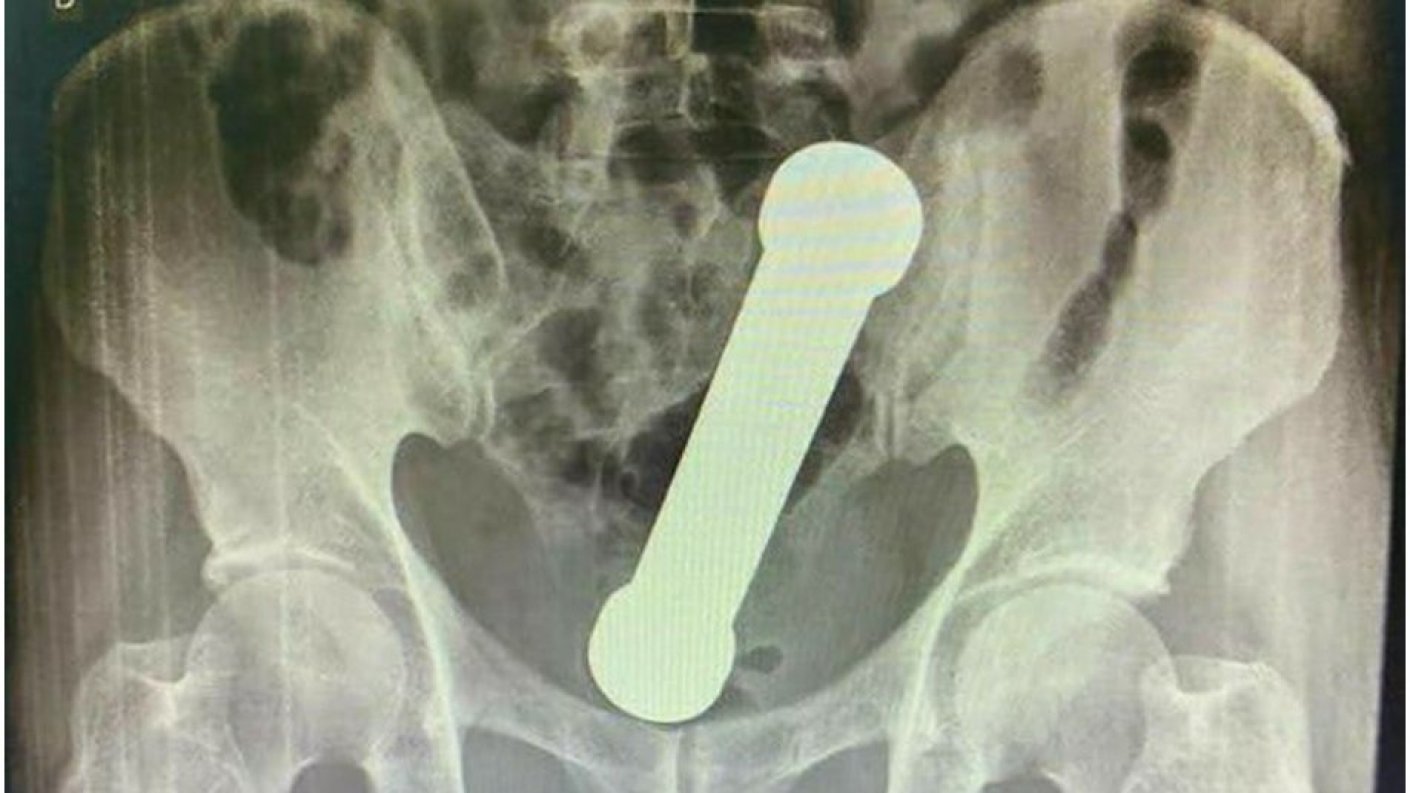

Tras realizarse un examen rectal que no entregó resultados concluyentes, se le realizó una radiografía, con lo que finalmente determinaron que tenía una mancuerna de dos kilos insertada en una parte profunda de su intestino grueso.

El hombre tenía una mancuerna de 20 centímetros atorada a la altura donde el colon se conecta con el recto que se había introducido dos días antes. ¿La solución? Los doctores realizaron una "extracción manual", donde uno de los funcionarios tuvo que introducir su antebrazo en el hombre.